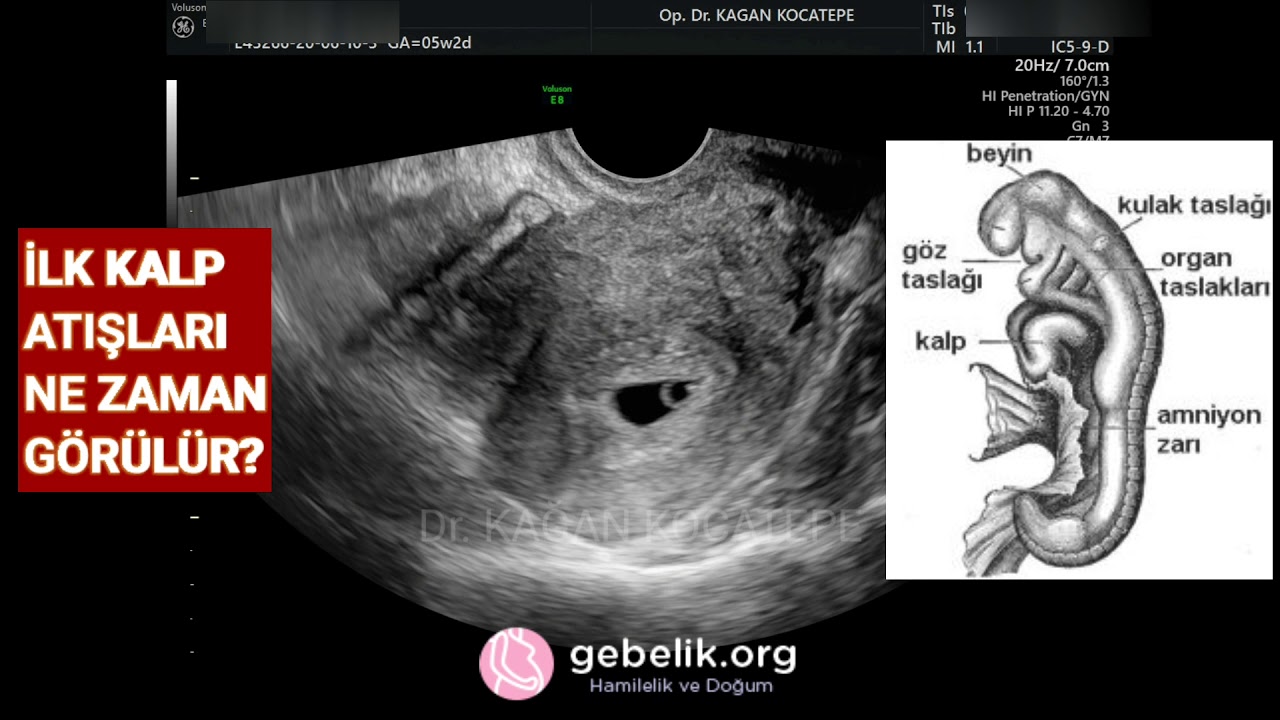

tüp bebekte kalp atışı ne zaman duyulur

tüp bebekte kalp atışı ne zaman duyulur.

bebegin ilk kalp atisi ne zaman duyulur annegram com